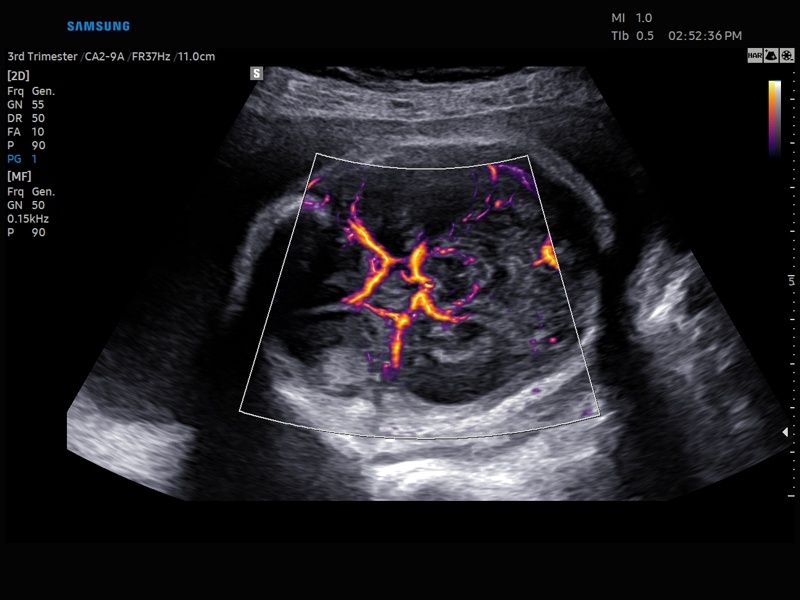

• Акушерство и гинекология

• Модуль MV-Flow – программа (режим), позволяющая визуализировать кровоток в микроциркуляторном русле с высоким разрешением без использования контраста.

• Модуль LumiFlow – программа отображения кровотока с объемной графикой для лучшего понимания архитектоники сосудистого русла.

• Модуль MV-Flow - программа (режим), позволяющая визуализировать кровоток в микроциркуляторном русле с высоким разрешением без использования контраста.